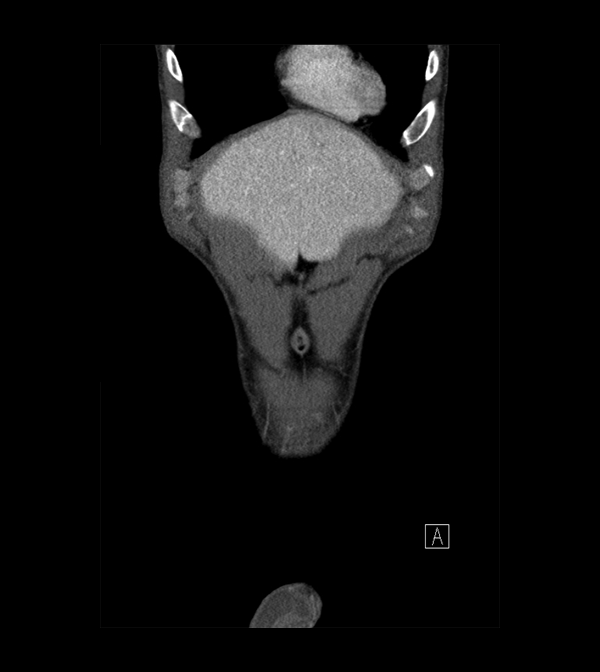

Pelvis